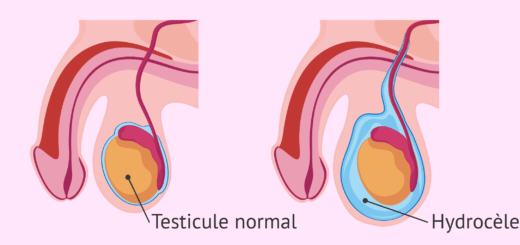

Une augmentation du volume d’une ou de vos deux testicules ? Des gènes et douleurs récurrents ? Il peut s’agir d’une hydrocèle. C’est l’accumulation d’un liquide dans la vaginale testiculaire ou simplement cette membrane...